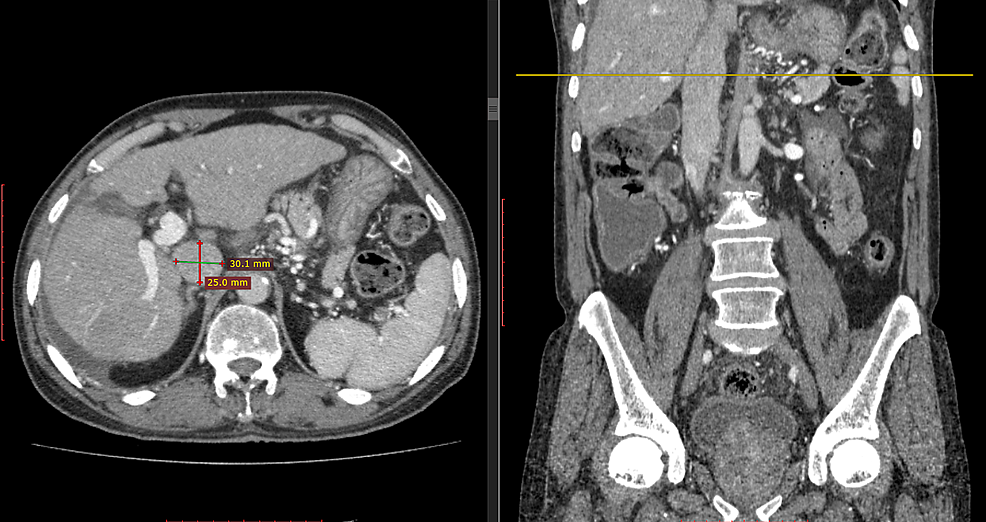

From www.spandidos-publications.com

Computed tomography manifestations of common inferior vena cava Normal Size Of Ivc The ivc is located to the right of the abdominal aorta, and most of the ivc lies in the retroperitoneal space. The inferior vena cava (also known as ivc or the posterior vena cava) is a large vein that carries blood from the torso and lower body to the. The inferior vena cava (ivc) is an essential but often overlooked. Normal Size Of Ivc.

Computed tomography manifestations of common inferior vena cava Normal Size Of Ivc The ivc is located to the right of the abdominal aorta, and most of the ivc lies in the retroperitoneal space. It is associated with a wide variety of congenital and pathologic. Ultrasonographic measurement of inferior vena cava (ivc) diameter and degree of respirophasic collapse was initially utilized by nephrologists. The inferior vena cava (also known as ivc or the. Normal Size Of Ivc.